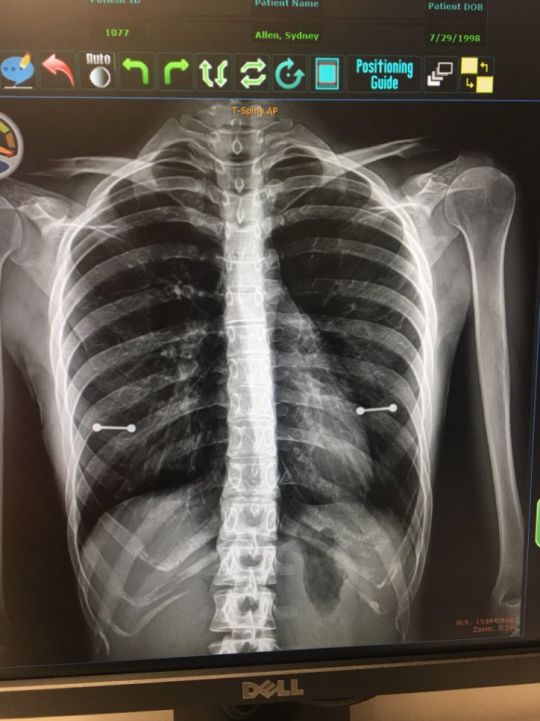

엑스레이 사진 때문에 부모님에게 가슴 피어싱을 한 사실이 들통난 여성.

영국 일간 메트로는 미국 플로리다 클리어워터에 거주 중인 시드니 앨런(20)의 사연을 소개했다.

시드지는 언니가 생일 선물로 준 가슴 피어싱을 하고 다녔는데 자매는 부모님에게 이 사실을 숨겼다고 한다.

하지만 그녀가 병원에서 찍은 엑스레이 사진 한장 때문에 피어싱을 한 사실이 들통나버렸다

그러나 이날 시드니가 피어싱을 빼는 것을 깜빡해 엑스레이에 피어싱이 고스란히 찍히고 말다고 한다.

시드니는 “엑스레이 사진 때문에 엄마가 피어싱을 확인했다. 의사와 나는 순간 빵 터졌지만 엄마는 진지하게 이따 얘기하자고 말했다”고 밝혔다.